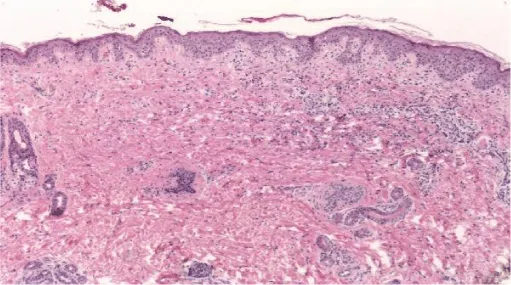

A skin biopsy reported: perivascular and interstitial vacuolar dermatitis, which is suggestive of cutaneous lupus (Figure 2). Antibodies anti-Sjögren, anticardiolipin, anti-DNA, and ANA were negative. However, anti-Ro was positive. At the same time, we ruled out the same antibodies in her mother.